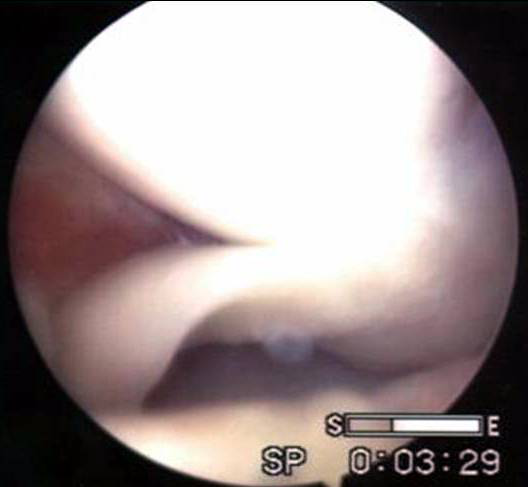

桶柄裂

探察桶柄裂

桶柄裂取出